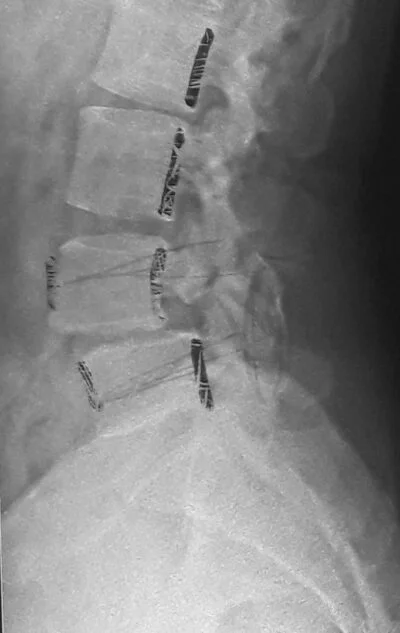

Commonly, plain x-rays of the spine may be ordered with or without some basic blood investigations such as hemoglobin, erythrocyte sedimentation rate [ESR], CRP, RA test, serum calcium, phosphorus and alkaline phosphatase.

Based on these tests, or sometimes, in the presence of some very significant signs or symptoms, you may be asked to undergo MRI scanning. Plain x-rays demonstrate bony features; while MRI demonstrates the spinal cord, its nerve roots, the intervertebral disc between the two bones of the spine. Both these tests are complimentary in nature; doing one does not necessarily mean that the other one is not needed.